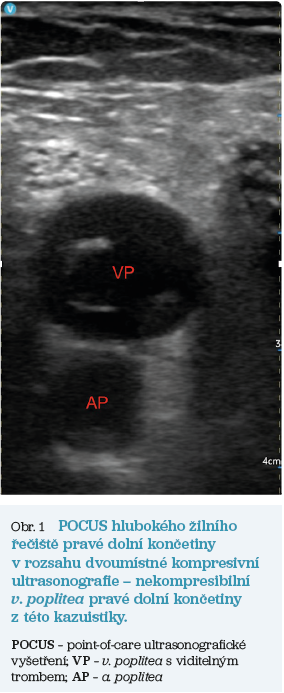

V říjnu 2022 pacientka přichází do ordinace všeobecného praktického lékaře pro dva dny trvající otok bérce levé dolní končetiny doprovázený zarudnutím a svěděním. Sama explicitně uváděla: „Tak mi to zase oteklo tou růží.“ Kromě toho se cítila unavená, ale neměla horečku ani zimnici a neuváděla žádné bolesti. Při vyšetření byla přiléhavě reagující, s tělesnou teplotou 37,0 °C, celkově zanedbaného vzhledu se známkami snížené osobní hygieny. Byla eupnoická s normálním poslechovým nálezem na plicích, normální oxygenací. Akce srdeční byla klidná a pravidelná, bez šelestu, tlak krve 145/95 mm Hg, tepová frekvence 77/min, kapilární návrat 3 s. Břicho bylo měkké, prohmatné, nebolestivé a bez rezistence. Na pravé dolní končetině byl patrný palpačně citlivý, nikoliv však bolestivý otok bérce s napjatou, zarudlou a lesklou kůží s drobnými varikozitami a s podkožními hemosiderinovými ložisky. Obvod bérce pravé dolní končetiny byl větší o 5 cm v porovnání s levou dolní končetinou, Homansův příznak byl oboustranně negativní, uzliny v třísle pravé dolní končetiny nehmatné. Obě dolní končetiny byly vizuálně zanedbané s četnými chronickými ragádami plosek nohou, onychomykotickými změnami nehtů prstců obou dolních končetin, meziprstní prostory mokvající se serózní sekrecí. Akra byla teplá, pulzace na a. dorsalis pedis a a. tibialis posterior hmatné, saturace arteriální krve kyslíkem (SpO2) byla 98 % na horní končetině a 98 % na prstci pravé dolní končetiny, pletysmografická křivka nevykazovala známky ischemie. Laboratorní hodnoty stanovené metodou POCT byly: C‑reaktivní protein (CRP) 98 mg/l, glykemie 12,6 mmol/l a D‑dimery 0,89 µg/ml. Záznam dvanáctisvodového EKG vyšetření (elektrokardiografie) prokázal fyziologický nález. Point‑of‑care ultrasonografické vyšetření (POCUS) hlubokého žilního řečiště pravé dolní končetiny v rozsahu dvoumístné kompresivní ultrasonografie prokázalo nález nekompresibilní v. poplitea a plně kompresibilního žilního řečiště v oblasti třísla (obr. 1). Nález na levé dolní končetině byl normální. Na základě provedených vyšetření byla stanovena pracovní diagnóza erysipel v oblasti bérce pravé dolní končetiny s komplikací v podobě hluboké žilní trombózy popliteálně vpravo.